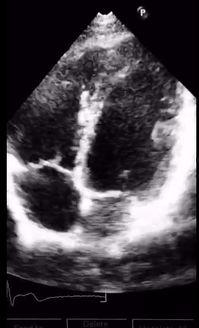

4. 听诊:医生将听诊器放在患者的胸部,仔细聆听心脏的跳动声音,判断心脏的节奏、强度和杂音等。